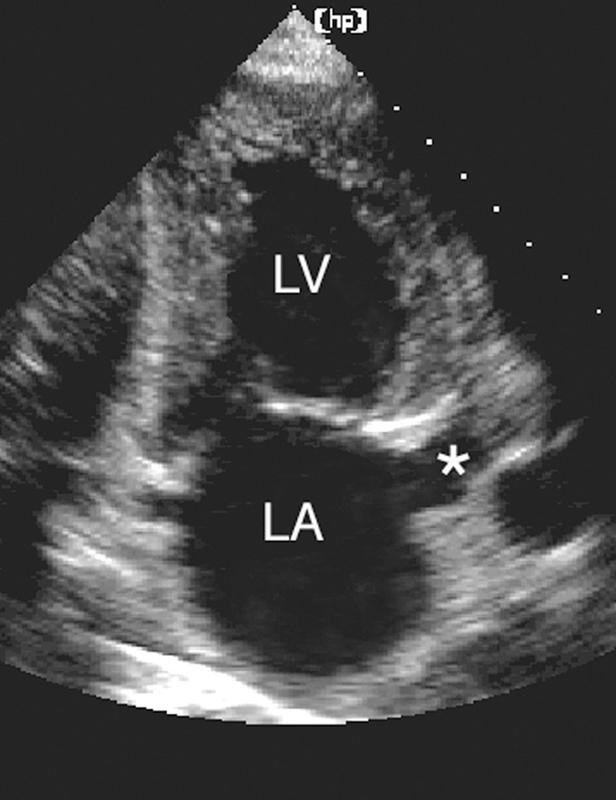

فحوصات تشخيصية لبعض امراض القلب والشرايين التاجية